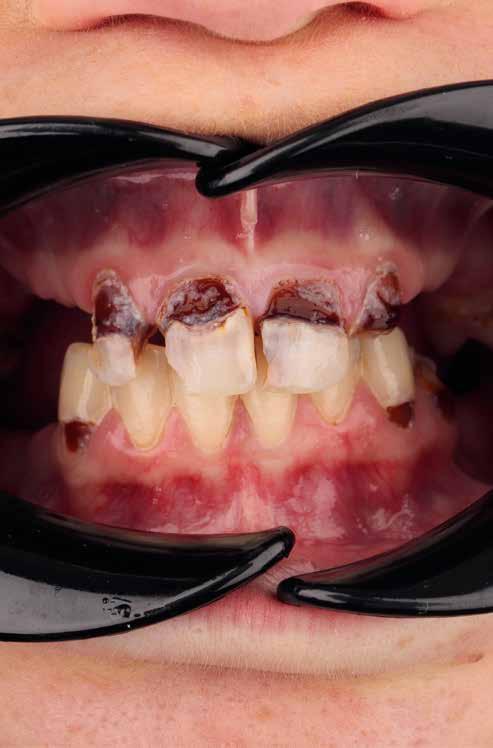

A cikkben egy fiatal nő kezelésének interdiszciplináris megközelítését foglaltuk össze, aki fogászati állapota miatt hoszszú ideje szenvedett fizikálisan és pszichésen is (1. ábra)

Amikor a 25 éves Andrea először konzultált a rendelővel, már több éve küszködött súlyos panaszokkal. Állapota két különböző betegségnek köszönhető, melyek egyrészt önmagukban, másrészt egymással kölcsönhatásban is súlyos következményekkel jártak. A fiatal nő veleszületett genetikai elváltozásban szenved, melynek tünete többek között a gyenge zománcfejlődés. Továbbá a beteget fibromyalgiával is diagnosztizálták, mely krónikus fájdalom rendellenesség, ami komoly tünetegyüttessel járó pszichés szorongás. A betegség egyik következménye az volt, hogy a páciens az elmúlt években átlagosan napi három-négyszer hányt. Az ebből fakadó savas erózió a már amúgy is veszélyben lévő fogazatot tovább roncsolta (2. ábra)

A betegség következményei

A páciens elviselhetetlen fájdalmakról számolt be, beleértve a többszörös szájüregi fertőzéseket is. Az elmúlt években az előírt számos antibiotikumos kezelés egyre gyengébb hatásfokkal működött. A fertőzések következtében több fogát is extrahálni kellett. A fogászati állapotával együtt az étkezés minősége is romlott. A súlyos esztétikai korlátok is terhet jelentettek. A psziché és az önbizalom komoly károkat szenvedett. Fogorvosnál tett korábbi látogatásai kellemetlen élményt jelentettek. Emiatt kezdetben vonakodott beleegyezni a komplex terápiába. Empatikus, érzékeny beszélgetések folyamán körvonalazódott számára a kezelés fontossága.

Sok konzultáció után definiáltuk az első kezelési célt: a nem megtartható fogak extrahálása és köztes helyreállítás ideiglenes fogsorral. A második kezelési fázisban implantátumok behelyezésére került sor. Elsősorban az életminőség javítása állt a középpontban. A páciens lehetőség szerinti komfortos kezelési menete és magas kiszámíthatóság biztosítása a team számára, vezetett a digitális fogászati megoldáshoz. Mivel a páciens egy pillanatig sem szeretett volna fogak

1. a–c ábrák: Kiindulási helyzet: fiatal páciens komoly fizikai és pszichés szenvedéssel.